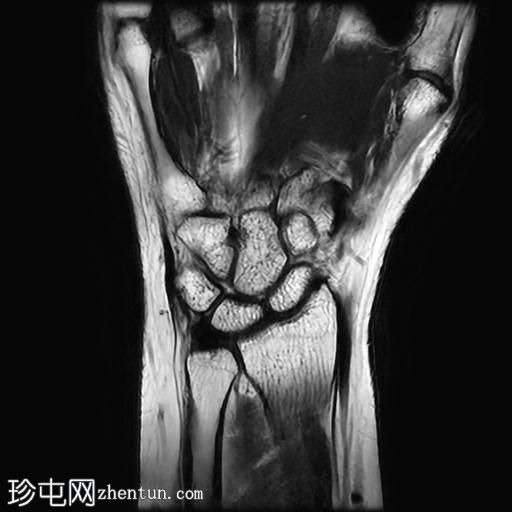

轴位

T1加权像

桡侧腕屈肌腱鞘内可见液体信号,提示腱鞘炎

手部桡侧腕屈肌腱远端扁平,邻近的大多角骨嵴和舟骨结节可见反应性骨髓水肿